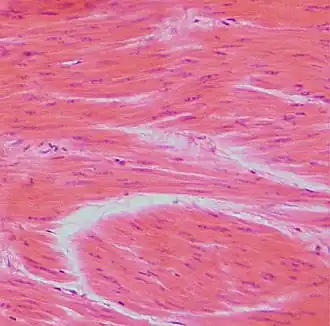

У некоторых беспозвоночных гладкие мышцы образуют всю мускулатуру тела. У позвоночных они входят в состав оболочек внутренних органов: кишечника, кровеносных сосудов, дыхательных путей, выделительных и половых органов, а также многих желёз. Клетки гладких мышц у беспозвоночных разнообразны по форме и строению; у позвоночных в большинстве случаев веретенообразные, сильно вытянутые, с палочковидным ядром, длиной 50—250 мкм, в матке беременных животных — до 500 мкм; окружены волокнами соединительной ткани, образующими плотный футляр.

Мышечные клетки называются миоцитами. Гладкие миоциты — веретенообразные вытянутые клетки, содержащие одно палочковидное ядро, расположенное в центре. Каждый миоцит окружён базальной мембраной[3].